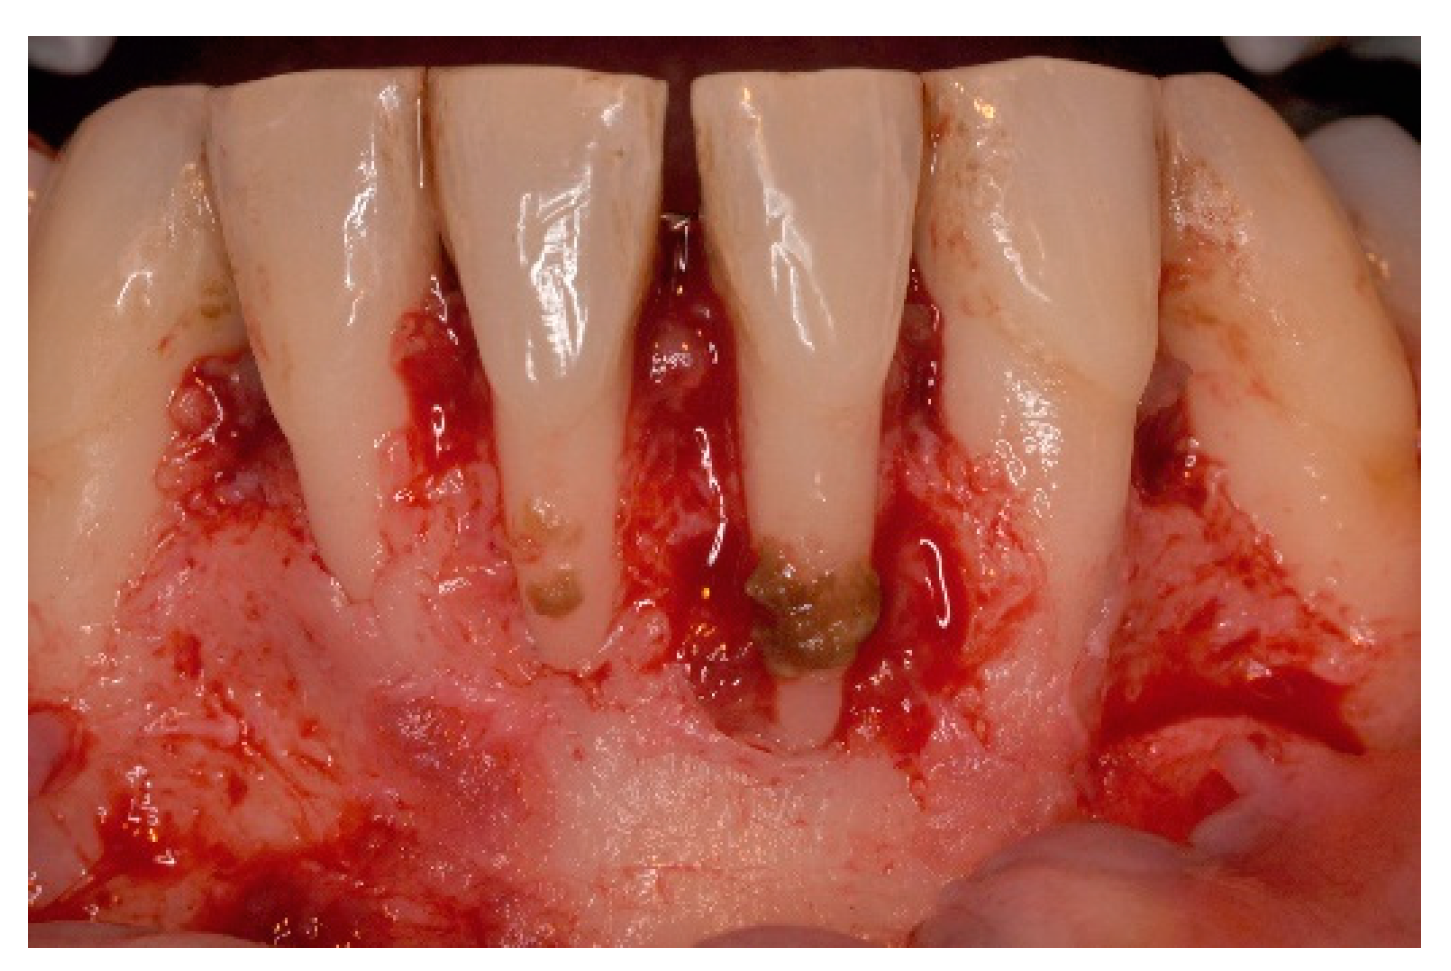

4. Free Connective Tissue Grafts in Periodontal Regenerative Procedures

5. Materials and Methods